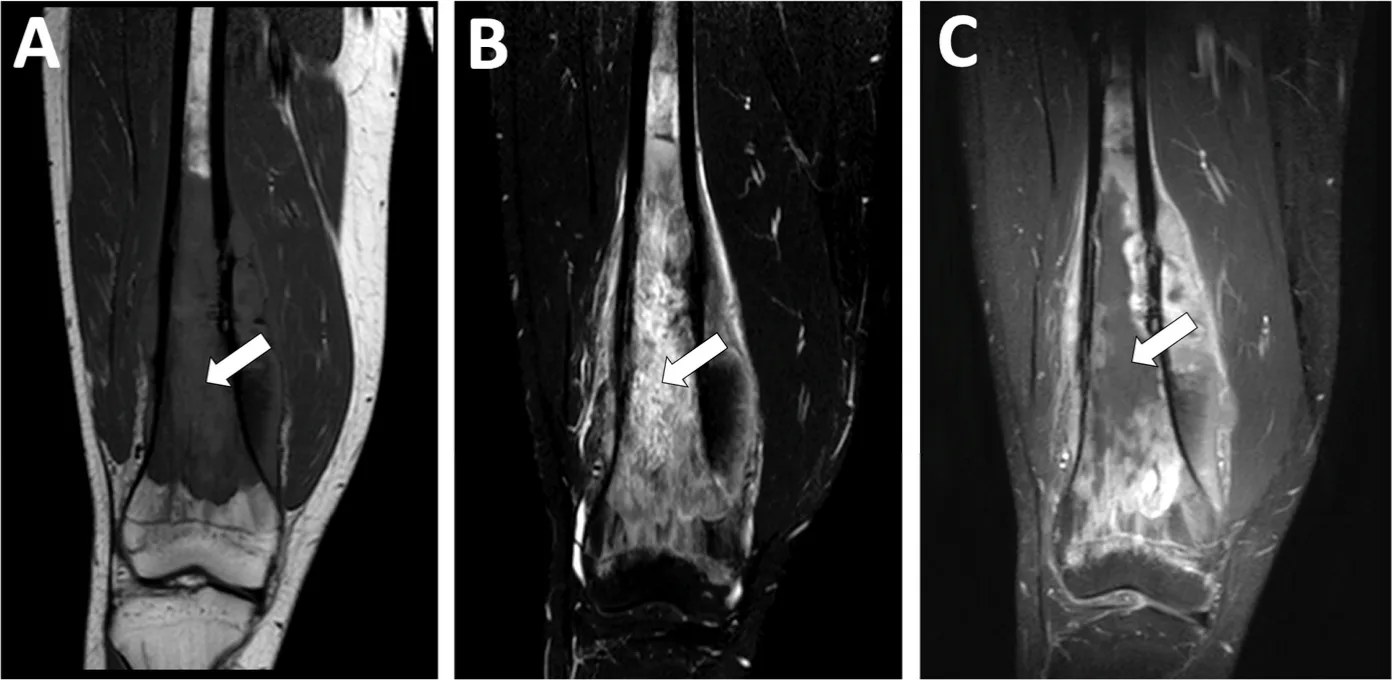

T1強調画像(A)では, 白く写る骨内の脂肪成分が灰色に変化しています.

T2強調画像(B)では, 骨内及び骨外の腫瘍が白く描出されています.

ガドリニウム造影像(C)では, 血管が増生している部分は白く描出される一方, 骨内の腫瘍の中央部は血行障害による壊死を生じていて, 造影効果が認められません.

送られてきたMRIを一目見て, 典型的な通常型骨肉腫の画像所見であることは明らかでした.